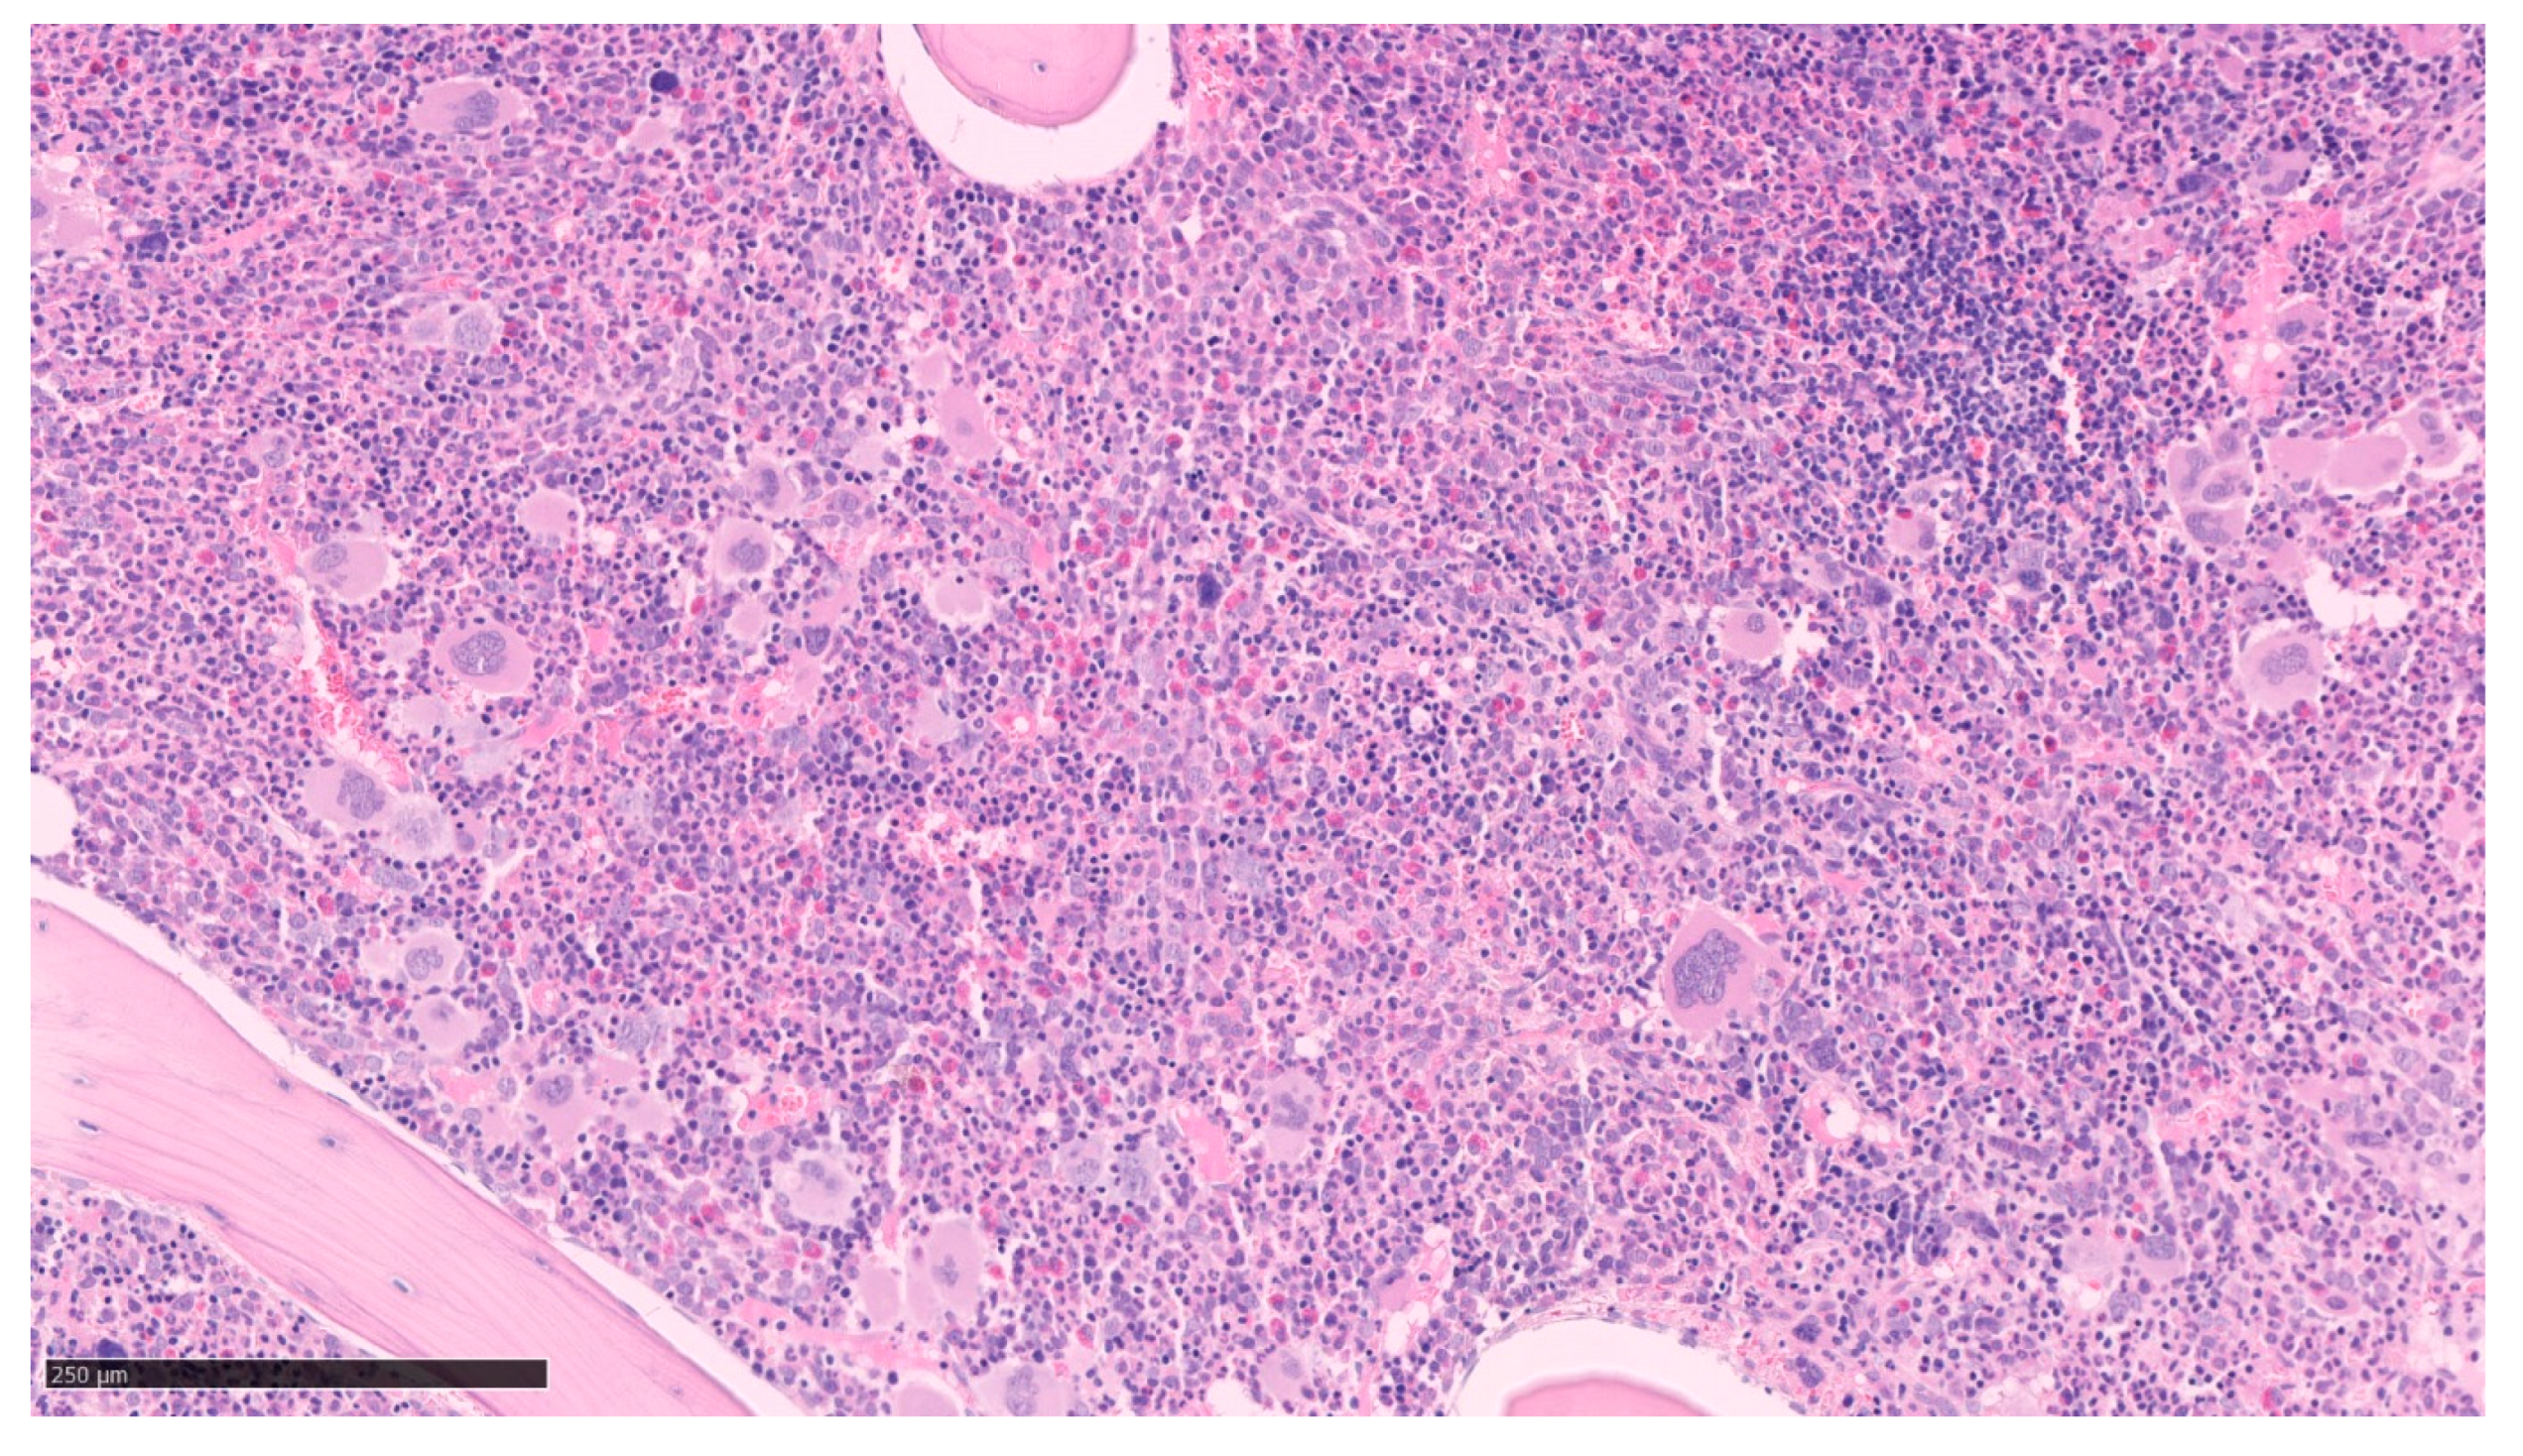

In the polycythemic phase, neutrophilia and rarely basophilia may be present on PB with occasional immature granulocytes but circulating blasts are usually not detected. The BM aspiration shows a trilineage hyperplasia (panmyelosis) with especially erythroid hyperplasia but without dyserythropoiesis. There is also slight granulocytic hyperplasia with no dysgranulopoiesis signs. At low magnification, we observe an increase in pleomorphic mature MKs with atypical features such as hyperlobulation and/or clusters formation as in Figure 1 [20,29]. The size of cells is very heterogenous without abnormal maturation. Pearl’s staining does not reveal any iron deposits.

Figure 1.

Bone marrow biopsy of Polycythemia Vera. Panmyelosis with an increase in pleomorphic mature megakaryocytes. (optical microscopy, May Grünwald Giemsa (MGG), low magnification ×15).